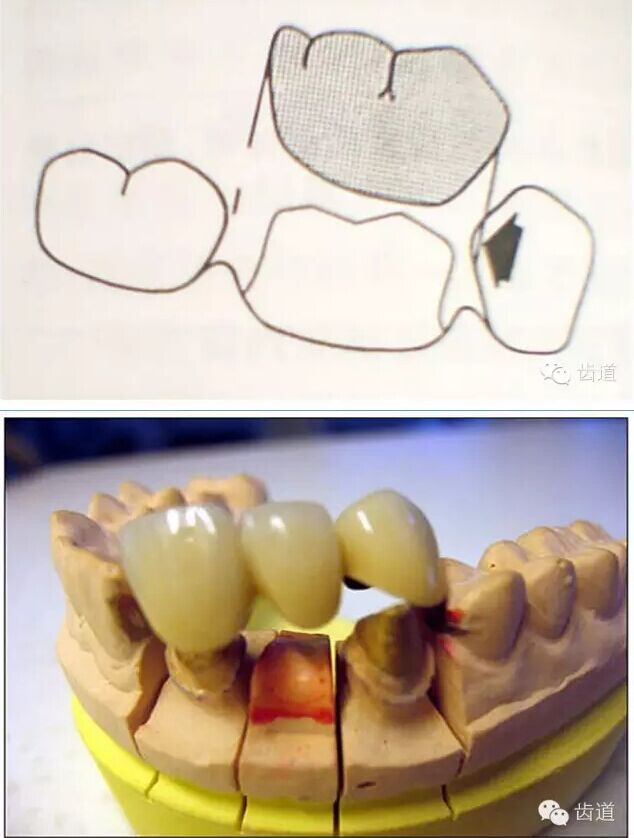

l預留修復體的空間

l多個基牙時就位道的調(diào)節(jié)

牙的外形及洞形的幾何形狀:主要是牙體制備出一定聚合角度產(chǎn)生的阻擋作用